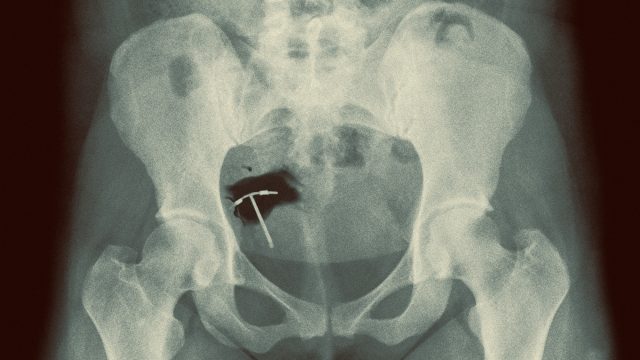

Hormonal coils, which release low levels of hormones into the body, are one of two types of contraceptive intrauterine device (IUD). The other is the so-called “copper” coil, which doesn’t release hormones into the body.

More than three-quarters of women find getting a coil fitted moderately or severely painful, a study in the Journal of Family Planning and Reproductive Health Care found. Research has long shown that doctors severely underestimate the pain of insertion.